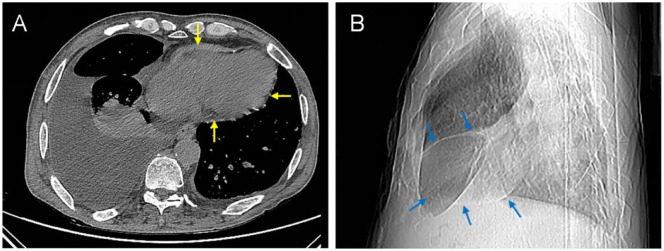

由于心包炎症和纤维化,缩窄性心包炎可导致舒张期心室充盈受损。收缩性心包炎的诊断需要通过超声心动图确定结构和血流动力学特征。我们报告了一例缩窄性心包炎病例,其表现形式为呼吸困难和下肢水肿在 7 年时间里逐渐加重。患者通过超声心动图确诊为缩窄性心包炎,并接受了心包切除术。

Constrictive pericarditis can lead to compromised diastolic ventricular filling due to pericardial inflammation and fibrosis. A diagnosis of constrictive pericarditis was established by identifying structural and hemodynamic features through echocardiography. We present a case of constrictive pericarditis, which manifested in the form of gradually worsening dyspnea and lower-extremity edema over a 7 years period. The patient was diagnosed with constrictive pericarditis using echocardiography, and underwent a pericardiectomy.